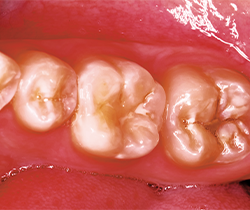

Fig. 5 Fig. 6

The bevel on the cavosurface margin allows for increased esthetics for the materials to have a chameleon effect with the underlying enamel. The resultant cavity preparation revealed preparations that were in excess of 4 mm deep in all prepared teeth. Once the caries were completely removed, the dentin and enamel were particle abraded with a PrepStart™ (Danville) with 40 micron aluminum oxide to homogenize the dentin, creating a uniform smear layer of the dentin forming the ideal interface for dentin bonding. The decision was made to use Tetric EvoCeram Bulk Fill (Ivoclar Vivadent) composite restorative.